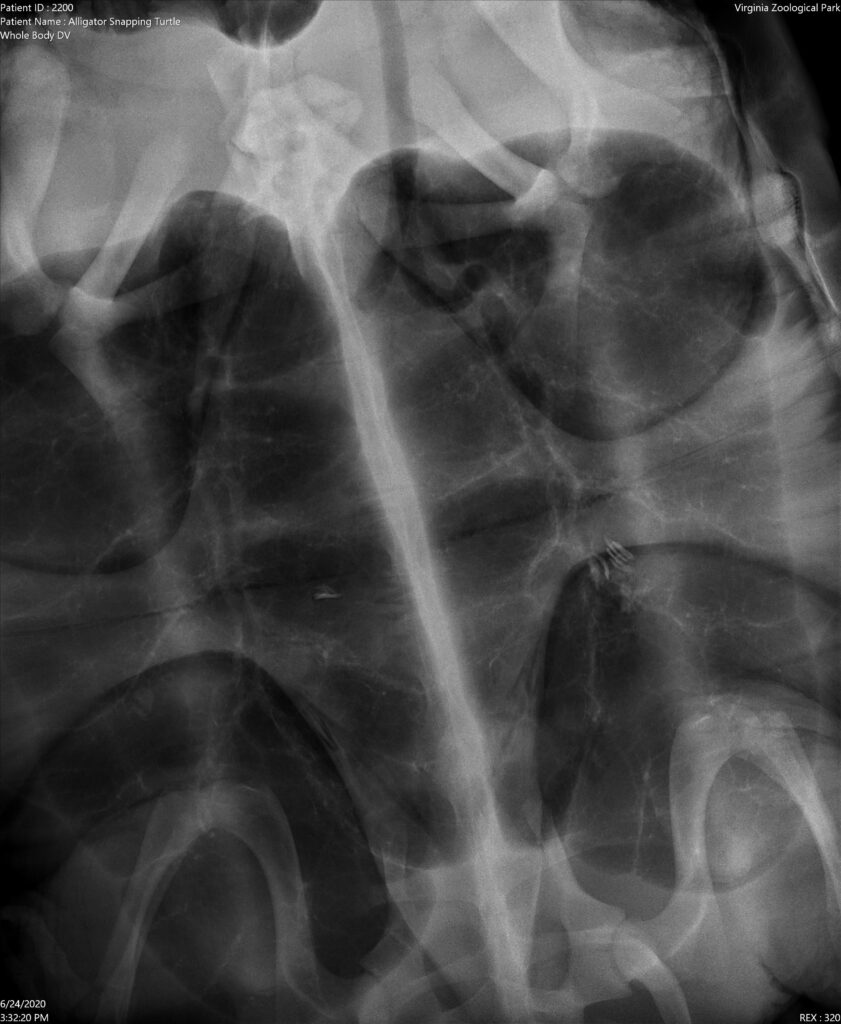

Just like all new arrivals at the Zoo, Yidaro is undergoing a routine quarantine period behind-the-scenes in the Zoo’s Animal Wellness Campus. To assess his overall condition and health, a wellness exam was scheduled immediately after arriving on grounds. During his exam, our animal care team looked over every inch of Yidaro’s body. Radiographs were taken to check for any foreign objects in his GI tract as well as to have a set of baseline images to compare with any radiographs taken in the future. Blood was taken as well for baseline chemistry, complete blood count values and to look for any potential illnesses.